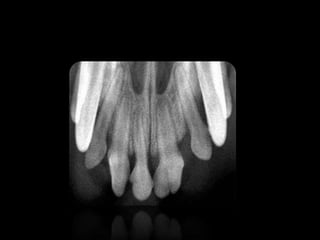

RIZOGÉNESIS INCOMPLETA